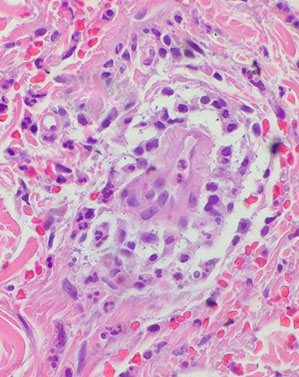

Porphyria cutanea tarda c festooning of the dermal papilla (protruding into the blister)

Subepidermal pauci-inflammatory vesiculation; thick acral skin c compact orthokeratosis;

- Caterpillar bodies - compact hyaline material

- festooning of dermal papillae (protrude into blister)

- hyalinization of blood vessels

Porphyria cutanea tarda (PCT)

MCC porphyria in the states; assoc c Hep C and AIDS, EtOH, iron overload and possibly inherited deficiency of uroporphyrinogen decarboxylase (in heme synth), which are found in the liver

- get blisters in sun-exposed areas (back of hands)